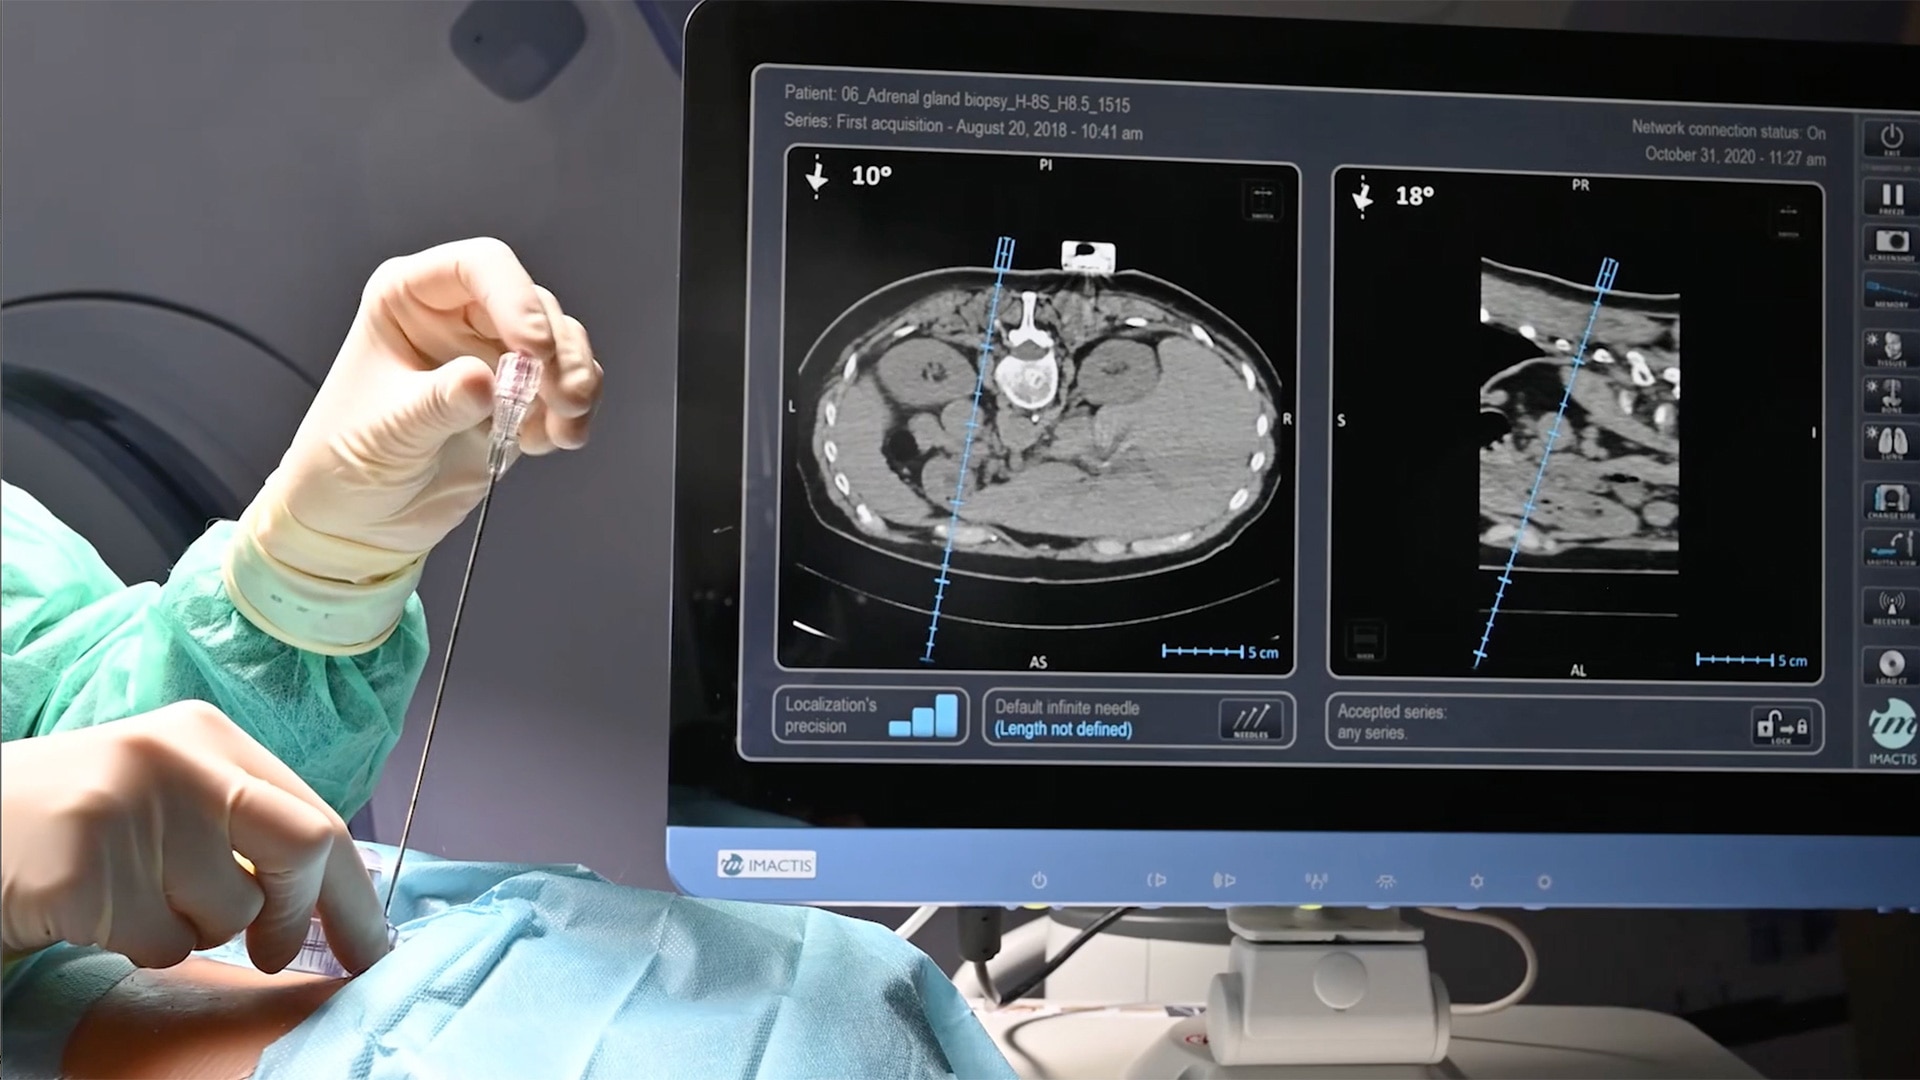

Accuracy

Improve accuracy to reach target and avoid critical structures and organs¹